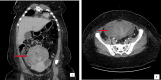

Syncope is a common emergency department (ED) chief complaint. Rarely, syncope can be the result of right ventricular outflow obstruction from an intracardiac tumor, such as an intracardiac extension of intravenous leiomyomatosis (IVL). Typically, this type of tumor is confined to the pelvic veins, but in very rare cases, it can extend through the inferior vena cava into the right atrium. Point-of-care ultrasound (POCUS) can be a crucial tool in the ED for identifying intracardiac tumors presenting as syncope and expediting clinical management. We present the case of a 39-year-old female with no prior medical history that presented to the ED having experienced dyspnea on exertion and two syncopal episodes prior to ED admission. POCUS use in the ED elucidated the presence of a right atrial mass and further imaging showed a mass on the patient's uterus. After surgical removal of a portion of the atrial mass, a subsequent biopsy revealed it had leiomyoma-like features; as such, the patient was diagnosed with IVL. This case illustrates the importance of using POCUS in the ED to help determine the etiology of syncope. Although intracardiac extensions of IVL are rare, it is important for emergency physicians to keep this diagnosis in the differential in patients with symptoms or risk factors suggestive of IVL with intracardiac extension.